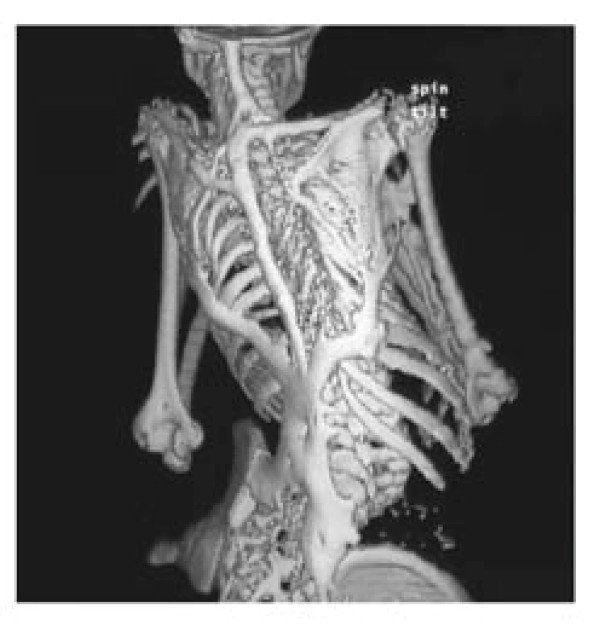

CT scan of human Heterotopic ossification. This is a disorder where the formation of ectopic bone happens in soft tissues of the musculoskeletal system due to an activating point mutation in ACVR1 gene, high energy traumatic injuries such as burn or blast wounds, invasive orthopedic cases, or severe brain and spinal cord injuries